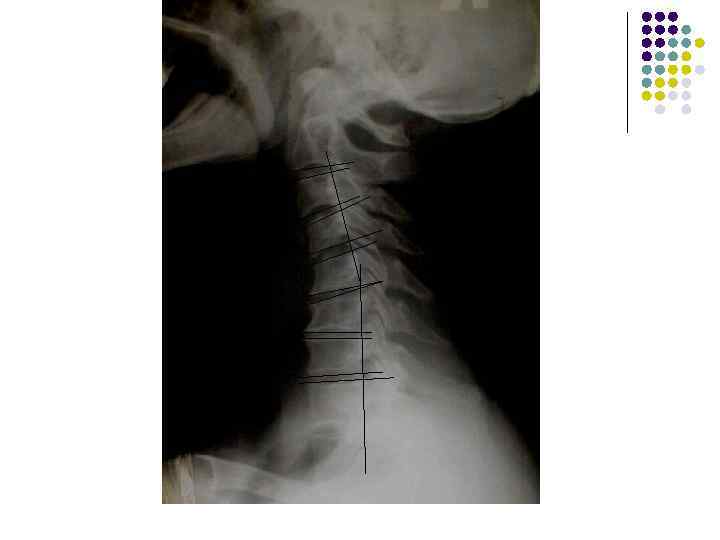

l l l На рентгенограмме шейного отдела позвоночного столба в боковой проекции определяется: выраженные распространенные дистрофические изменения в виде остеохондроза и артроза дугоотростчатых суставов: неравномерное сужение межпозвонковых пространств, субхондральный остеосклероз, костные разрастания по краям тел позвонков, сужение рентгеновских суставных щелей дугоотостчатых суставов с субхондральным остеосклерозом и небольшими костными разрастаниями по краям суставных поверхностей. Наиболее ярко эти изменения выражены в сегментах С 5 -6 -7 Признаки ограниченного смещения тел позвонков в виде симптома «распорки» и кифотической установки. Заключение: Остеохондроз шейного отдела позвоночного столба. Артроз дугоотростчатых суставов. Деформация шейного отдела позвоночника с нарушением статики.

1.

l l l На рентгенограмме шейного отдела позвоночного столба в боковой проекции определяется: выраженные дистрофические изменения за счет остеохондроза - значительное, неравномерное сужение межпозвонковых пространств с нарушением их правильной клиновидной формы, выраженный субхондральный остеосклероз, значительные костные разрастания по передним краям тел позвонков. Наиболее ярко эти изменения представлены в сегментах С-5, 6, 7. Помимо этого, в этих же сегментах фиксируются дистрофические изменения дугоотростчатых суставов – сужение рентгеновских суставных щелей, субхондральный остеосклероз и костные разрастания по краям суставных поверхностей. Выпрямление физиологического лордоза. Признаки системного нарушения статики тел позвонков в виде симптомов кифотической установки. Деструктивных изменений нет Заключение: Комплекс дистрофических изменений шейного отдела позвоночного столба в виде остеохондроза и артроза дугоотростчатых суставов с преимущественными проявлениями в нижних сегментах отдела. Нарушение статики тел позвонков

3.

l На рентгенограмме шейного отдела позвоночного столба в боковой проекции определяется: выраженные дистрофические изменения за счет остеохондроза с преимущественными проявлениями в сегменте С 5 -6 – сужение и деформация межпозвонковых пространств, выраженный субхондральный остеосклероз, значительные костные разрастания по краям тел позвонков. Выпрямление физиологического лордоза. Признаки нарушения положения тела С 4 (симптом «распорки» )